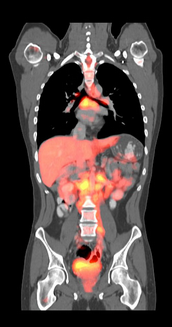

When displaying volume data, it may be beneficial to merge the visualizations of two different datasets into a single image. A use case example is the fusion of PET and CT datasets to better visualize tumor locations in the body. The XStream® HDVR® SDK provides utility functions to support rendering images from separate datasets, and blending images from these datasets into a fused image. This feature is referred to as 2D Fusion because it produces a 2D image from separate 3D datasets. The datasets to be used for the fused image do not need to be registered, have the same voxel size, or the same initial orientation.

2D_Fusion

PET/CT Fusion